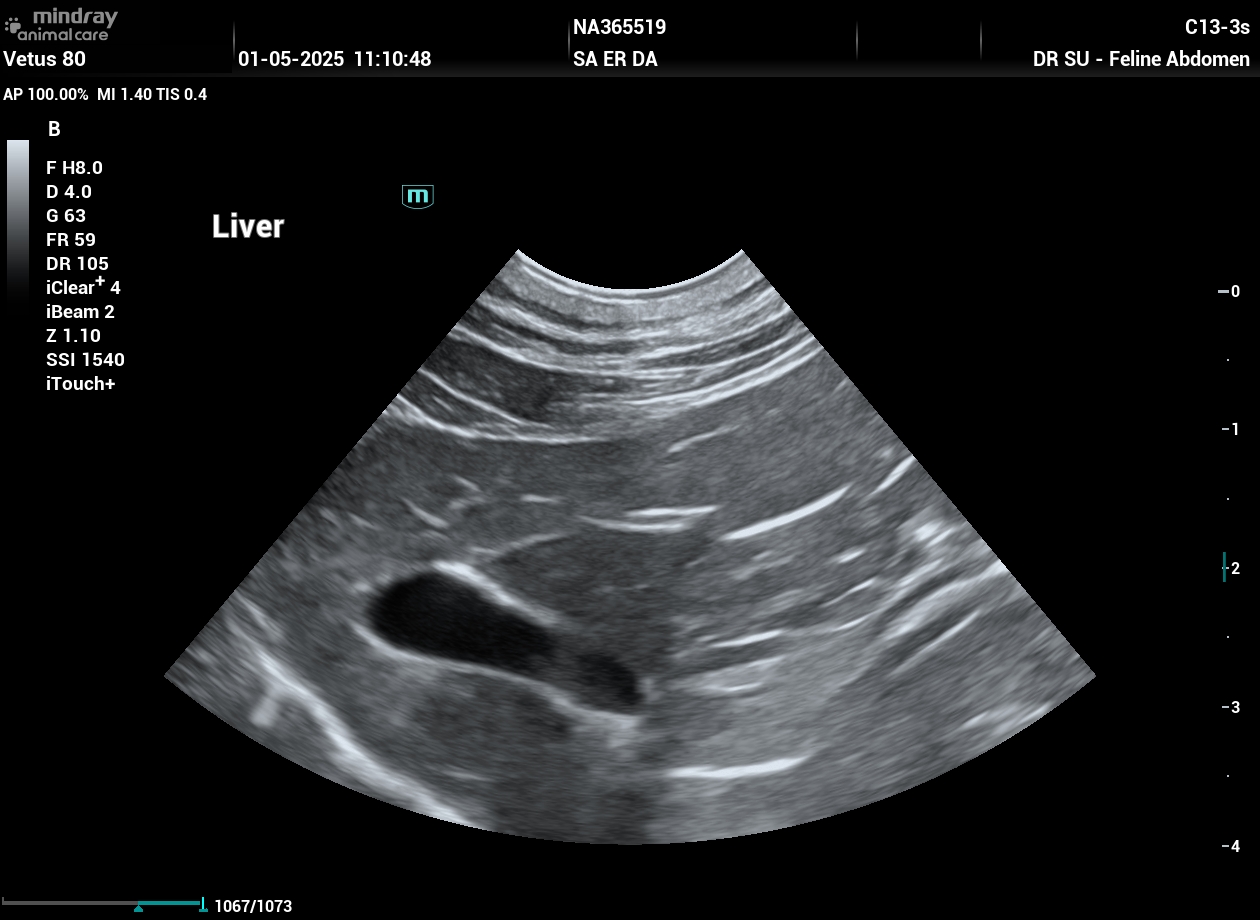

202505011111000033ABD.JPG